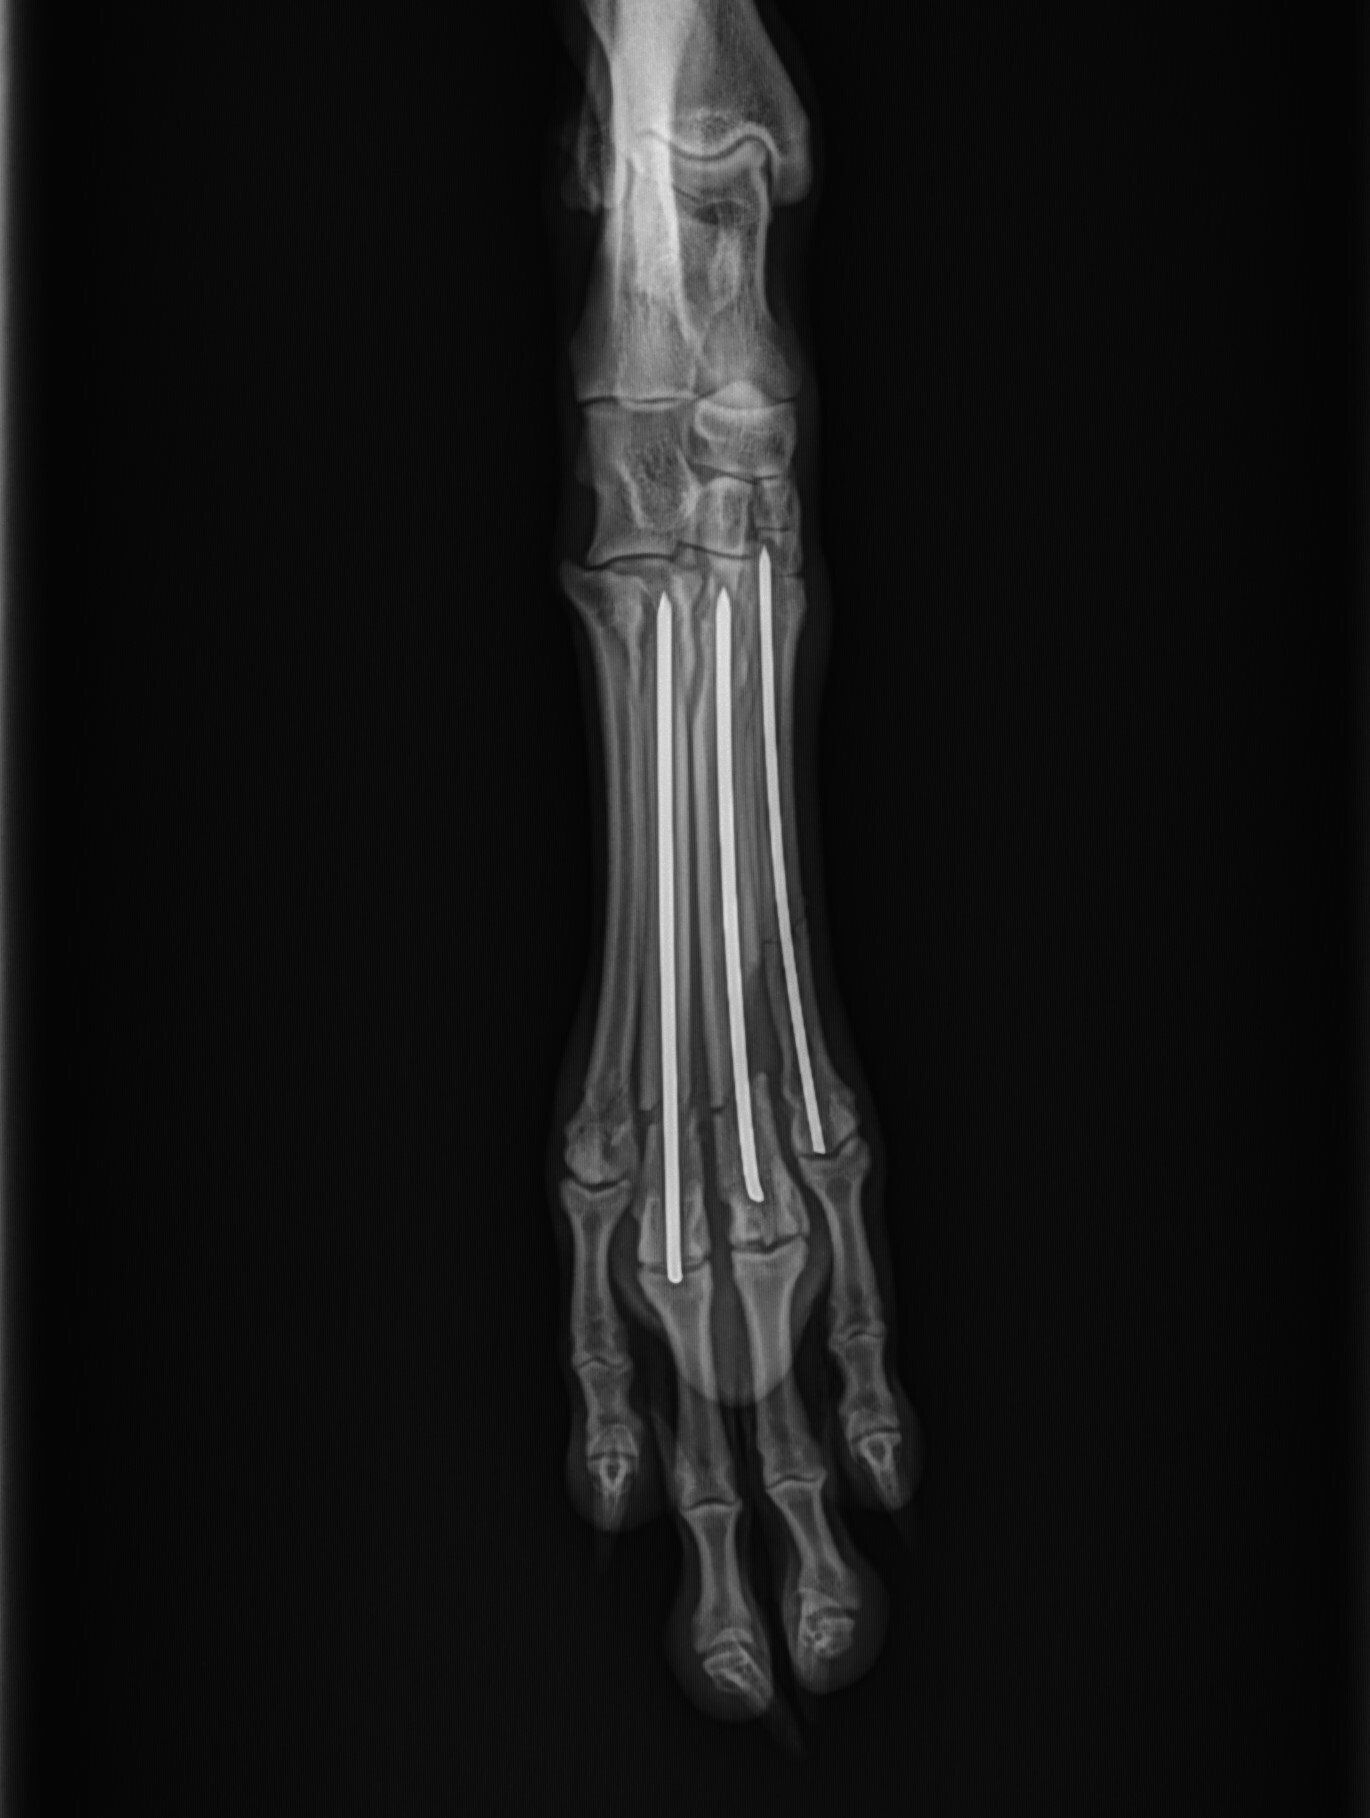

Leg fractures are one of the most common orthopedic problems presented at our clinic and usually result from a traumatic mishap. They can be treated in a variety of ways depending on the location and type of fracture. We can apply a cast to treat certain fractures; however, many fractures will require surgical intervention:

- “Pinning” stabilizes the fracture by inserting a long stainless steel rod into the middle of the bone across the fractured area.

Below are x-rays of just a few orthopedic surgeries before and after that Dr. Gose has performed.